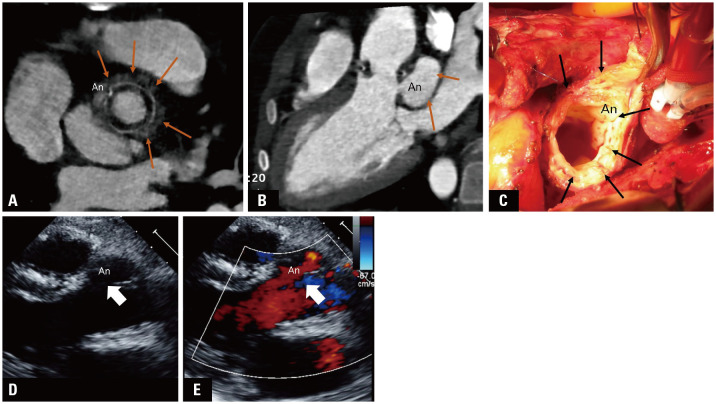

Aortic regurgitation (AR) in children is usually caused by congenital valve anomalies, and Behçet syndrome (BS) can be suspected in cases of isolated AR. Patients with BS undergoing aortic valve surgery due to aortic valve invasion have a high risk of complications, such as leakage around the valve and dehiscence. Cardiovascular involvement occurs in 7%-46% of adult patients with BS and is the main cause of mortality; however, its prevalence is unclear and rare in children. A 12-year-old boy was diagnosed with severe AR associated with BS. A progressive subaortic pseudoaneurysm was observed after aortic valve replacement. The periaortic intracardiac pouch was at risk of rupture; therefore, the patient underwent a Bentall operation. After the Bentall procedure, a newly developed subaortic pseudoaneurysm was detected below the prosthetic valve. However, the risk of rupture reduced as the subaortic pseudoaneurysm regressed with anti-inflammatory drugs alone without reoperation. Repeated surgery is inevitable in patients with BS undergoing aortic valve surgery due to the progressive chronic inflammatory reactions that present with a pseudoaneurysm. Here, we report an 8-year follow-up of a pediatric case of BS with subaortic pseudoaneurysm, highlighting the importance of close follow-up, medical management, and early diagnosis in treating this condition.

Abstract Image